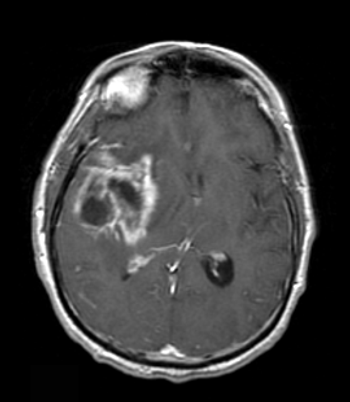

The patient is a 58-year-old woman who was diagnosed at an outside hospital with a World Health Organization (WHO) grade III non–contrast-enhancing right frontal anaplastic astrocytoma, with spread into the genu of the corpus callosum.